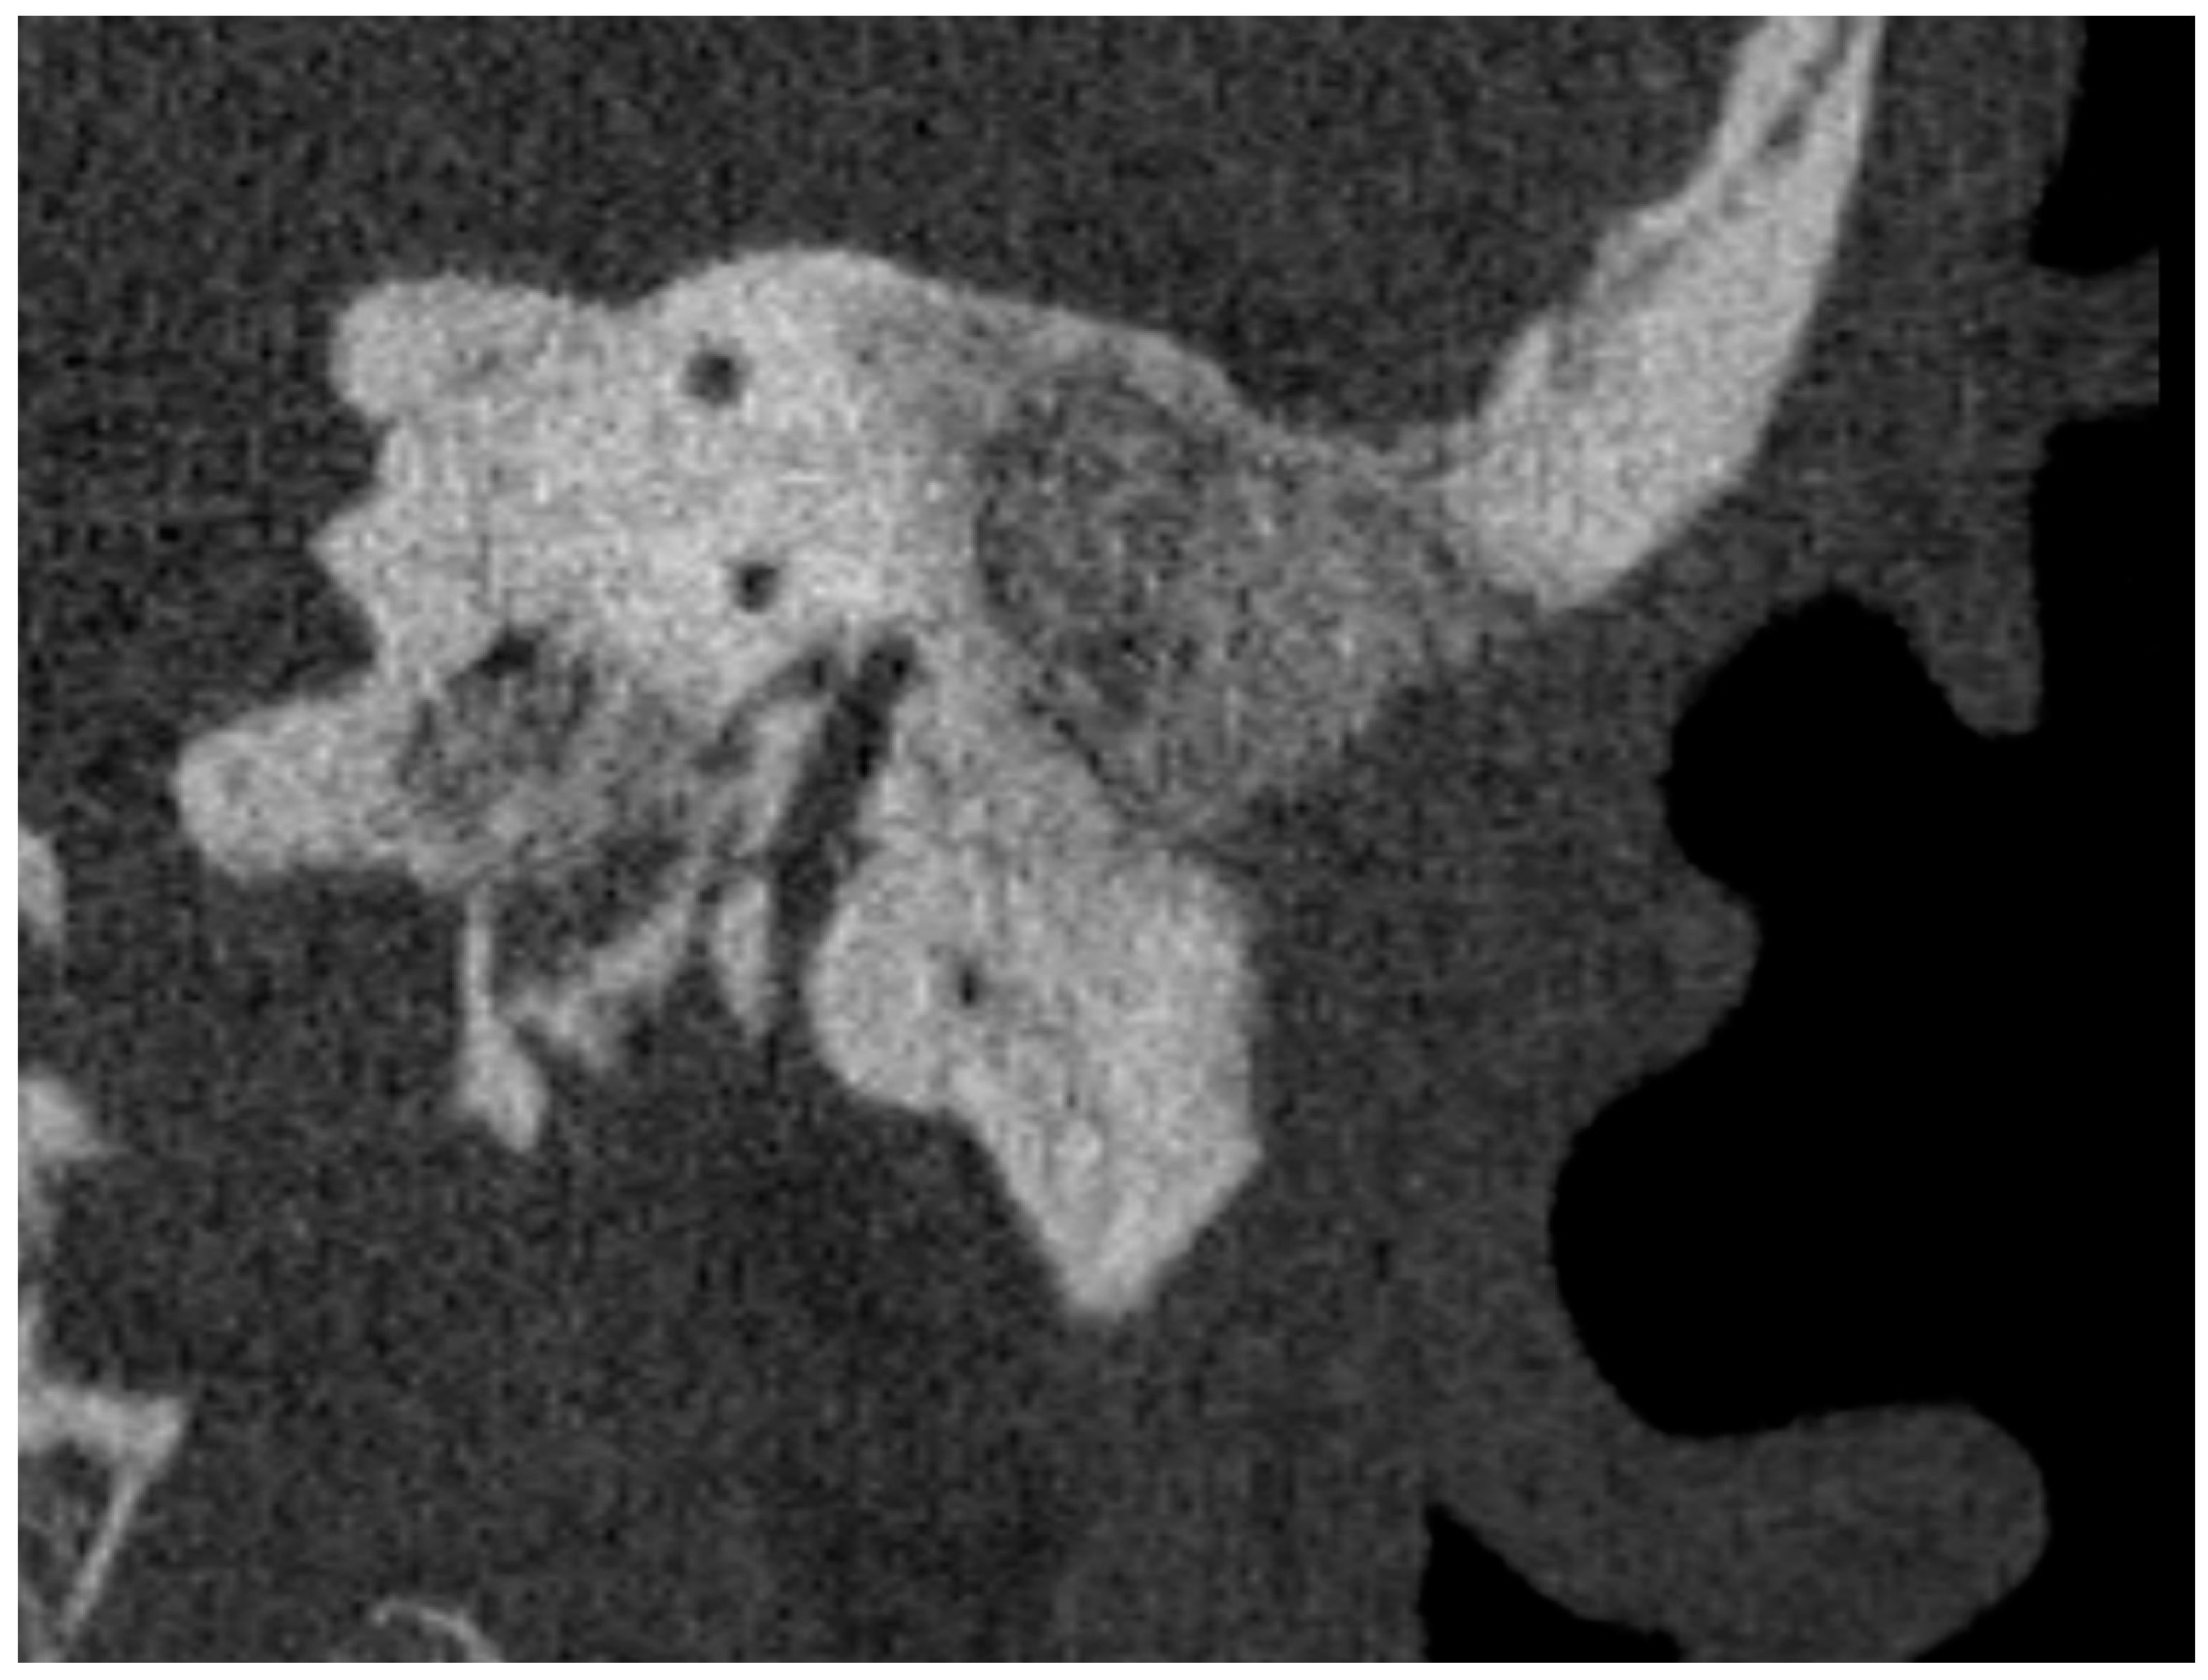

Micro- and videotoscopic examination three months after the surgery showed a healed reconstruction of the posterior wall of the ear canal in all patients, with no signs of leakage of granulation tissue and no pain. After six months, otoscopic examination showed no signs of pathology, and control swabs from smears of the operated ear were negative (Table 1). A control high-resolution CT was performed which showed complete healing of the surgical site, and no bone destruction was found, suggesting no recurrence of cholesteatoma (Figure 1).

Figure 1. Cross-section of the left temporal bone in the sagittal plane with the area filled with bioactive glass.

HRCT performed six months after obliteration showed no recurrence of cholesteatoma or displacement of the bioactive S53P4 in any of the cases; we did not notice any inflammatory reaction [17,28,36], bone erosion, or destruction, so there was no suspicion of recurrence of cholesteatoma. We therefore departed from the presumed necessity [39] to perform an MRI in these patients. In our clinic, performing an HRCT after reconstruction is necessary due to the need to evaluate the healing of the bioactive glass and to assess the anatomical conditions for the Bonebridge FMT. In case of doubt, the patient is immediately referred for a comparative MRI examination, which has greater sensitivity [39].